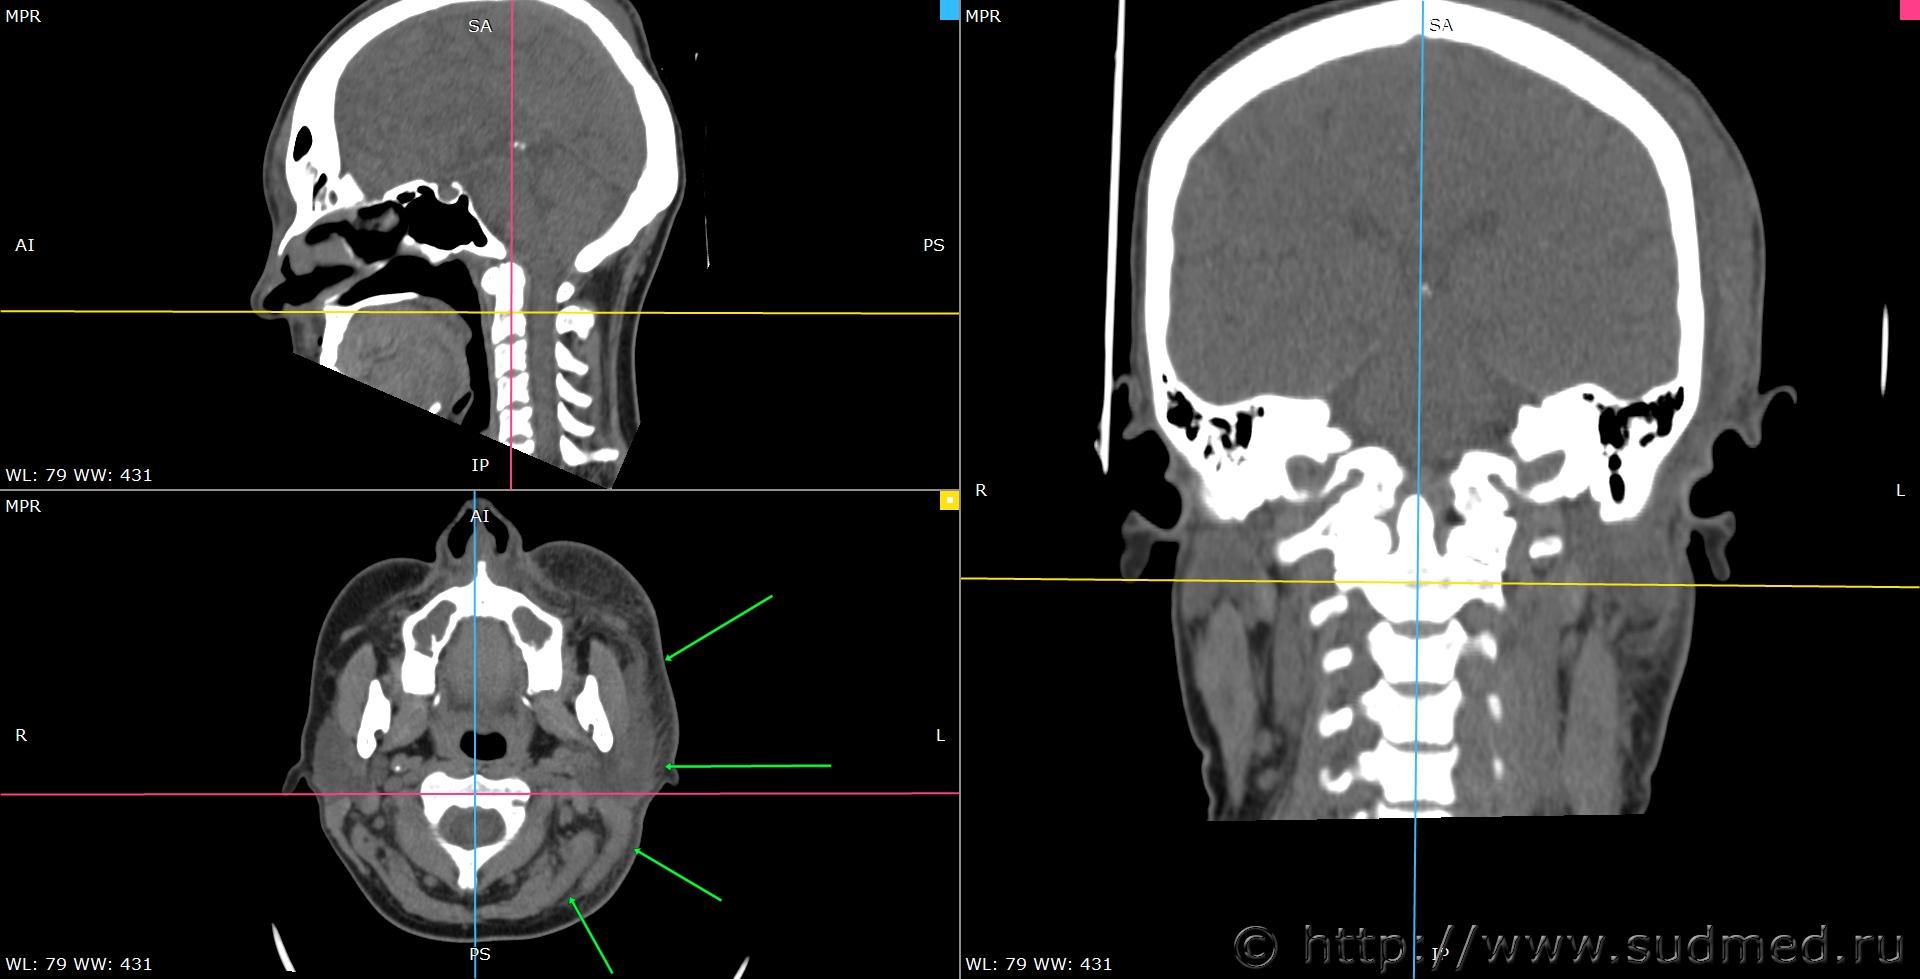

При экспертизе живого лица по медицинским документам встретились переломы шиловидных отростков височных костей. Женщина 39 лет, обратилась за медицинской помощью на 5-е сутки после травмы, тогда же провели РКТ. До этого никуда не обращалась. В протоколе РКТ отметили перелом шиловидного отростка левой височной кости, на снимках перелом на границе верхней и средней трети, дистальный отломок слегка смещен кпереди, каких-либо признаков заживления нет. Длина отростка 2,19 см. Судебная медицина - Прикрепленное изображение Также на КТ визуализируется перелом шиловидного отростка правой височной кости в нижней трети с выраженным смещением, думаю, отрывного характера (его длина 2,01 см), также без каких-либо признаков заживления Судебная медицина - Прикрепленное изображение; и гематома теменной области слева с переходом, в частности, на левую височную область, область левого сосцевидного отростка, левые околоушно-жевательную и скуловую области, левую боковую поверхность шеи Судебная медицина - Прикрепленное изображение, увеличение в объеме, нечеткость контура и разволокнение левой грудино-ключично-сосцевидной мышцы и левой ременной мышцы головы в верхней трети Судебная медицина - Прикрепленное изображение, вокруг них, в том числе кнутри от ременной мышцы, повышение плотности ПЖК Судебная медицина - Прикрепленное изображение; такие же изменения плюс повышение плотности левой подкожной мышцы шеи Судебная медицина - Прикрепленное изображение, увеличение в объеме и нечеткость контура левой околоушной слюнной железы, левая жевательная мышца не изменена Судебная медицина - Прикрепленное изображение. У подъязычной кости вижу нарушения целостности левого большого рога, но окостенение не завершено, края четко не визуализируются, поэтому о характере нарушений целостности не могу судить. Судебная медицина - Прикрепленное изображение Судебная медицина - Прикрепленное изображение В осмотрах врачей какие-либо изменения в области шеи, изменения голоса, соответствующие жалобы не отмечены; на 6-е сутки выставили острый фарингит. Помимо этой травмы есть переломы костей носа, там ничего особенного.